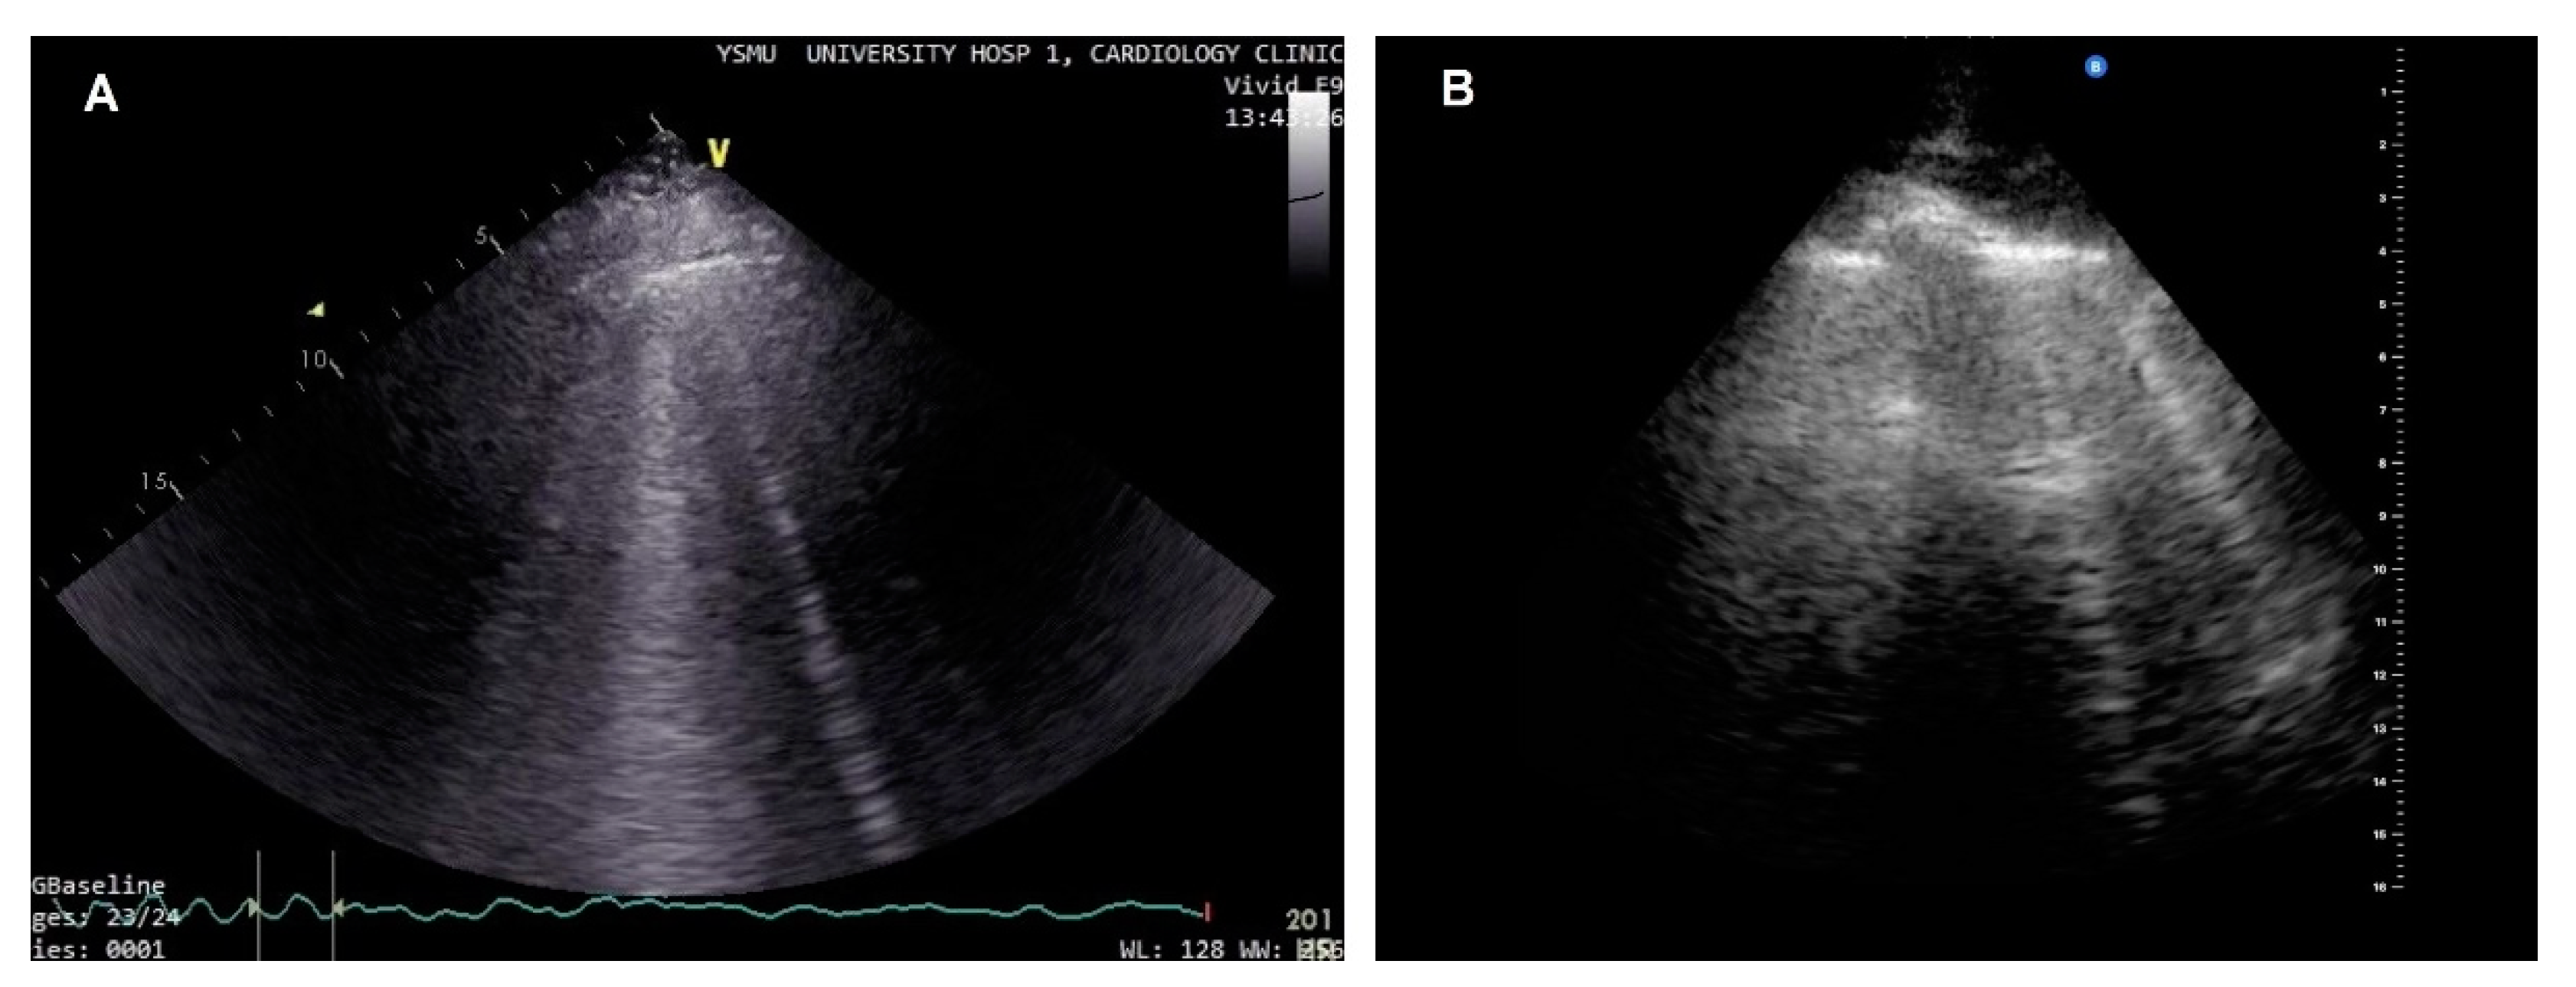

- Picano, E.; Pellikka, P.A. Clinical update Ultrasound of extravascular lung water : a new standard for pulmonary congestion. Eur Heart J. 2016, 37, 2097–104. [Google Scholar] [CrossRef]

- Volpicelli, G.; Lichtenstein, D.A.; Kirkpatrick, A.W.; et al. International evidence-based recommendations for point-of-care lung ultrasound. Intensive Care Med. 2012, 38, 577–91. [Google Scholar] [CrossRef] [PubMed]

- Coiro, S.; Rossignol, P.; Ambrosio, G.; et al. Prognostic value of residual pulmonary congestion at discharge assessed by lung ultrasound imaging in heart failure. Eur J Heart Fail. 2015, 17, 1172–1181. [Google Scholar] [CrossRef] [PubMed]

- Gargani, L.; Pang, P.S.; Frassi, F.; et al. Persistent pulmonary congestion before discharge predicts rehospitalization in heart failure : a lung ultrasound study. Cardiovasc Ultrasound. 2015, 13, 40. [Google Scholar] [CrossRef]

- Miglioranza, M.H.; Picano, E.; Badano, L.P.; et al. Pulmonary congestion evaluated by lung ultrasound predicts decompensation in heart failure outpatients. Int J Cardiol. 2017, 240, 271–278. [Google Scholar] [CrossRef] [PubMed]

- Platz, E.; Lewis, E.F.; Uno, H.; et al. Detection and prognostic value of pulmonary congestion by lung ultrasound in ambulatory heart failure patients. Eur Heart J. 2016, 37, 1244–1251. [Google Scholar] [CrossRef]